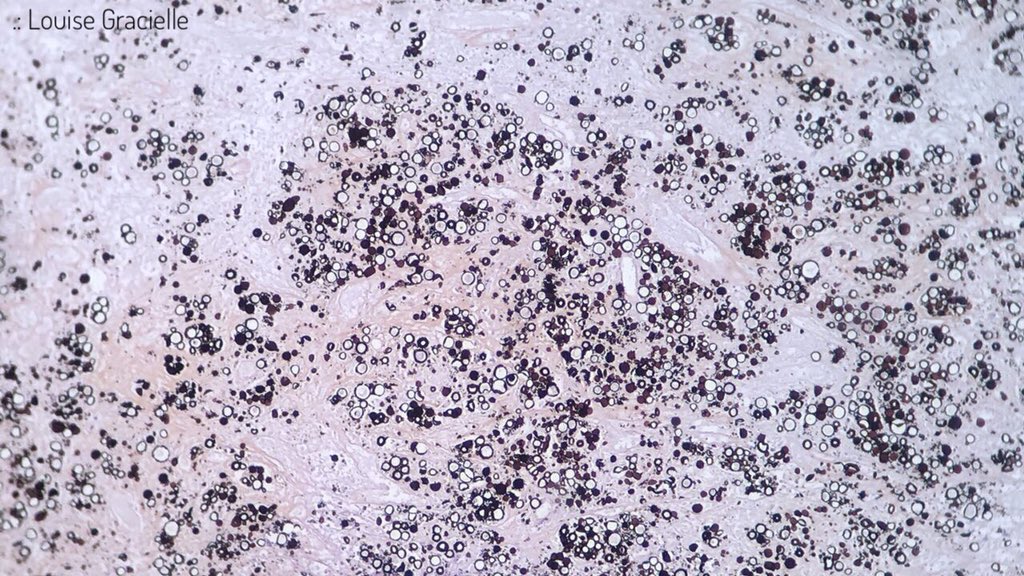

It looks like Paracoccidioides brasiliensis is throwing a party to which I wasn’t invited. 🎉🔅🔆🔅🎉 (Thank God! 😬) #Lymphnode #Yeasts #Paracoccidioidesbrasiliensis #Grocott #Pathology #ItLooksLikeAPainting

LouiseGracielle's tweet image. It looks like Paracoccidioides brasiliensis is throwing a party to which I wasn’t invited. 🎉🔅🔆🔅🎉

(Thank God! 😬)

#Lymphnode #Yeasts #Paracoccidioidesbrasiliensis #Grocott #Pathology #ItLooksLikeAPainting